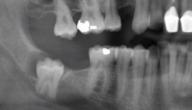

- نمو ضرس العقل بالطمر لعدم توفر مسافة كافية لظهوره، ويكون إما بشكلٍ مائل أو عامودي أو أفقي.

- أن يكون الضرس منطمراً تماماً، بحيث لا يظهر نهائياً في الفم.

- أن ينطمر الضرس بشكلٍ جزئي، إذ يظهر جزءاً من تاج الضرس في الفم، والجزء الآخر ينطمر داخل اللثة.